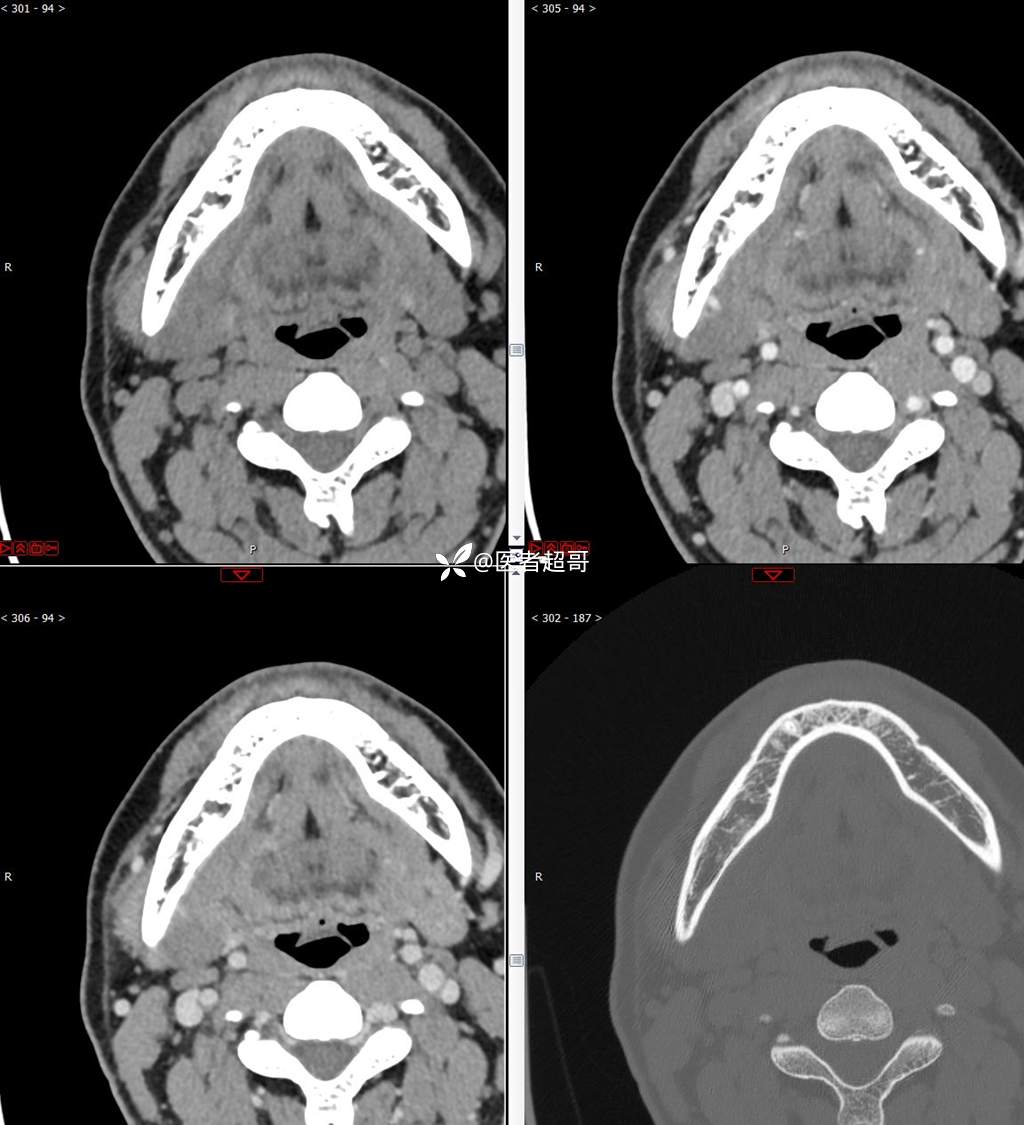

颌下腺结节:青年男性,颌下区无痛性肿物,请分析~~~

主 诉:发现右颌下区无痛性肿物1年。

现病史:患者于1年前发现右颌下区一肿物,肿物约“葡萄粒”大小,无疼痛不适,无进食时颌下区肿胀及疼痛不适。2023-10-1就诊于市中医院行超声检查;未予治疗。肿物体积无明显变化,求进一步治疗就诊于我院门诊,门诊以“颌下肿物”收入我科。患者自发病以来,神志清,精神佳,食欲好,睡眠好,大小便正常,近期体重无明显变化。